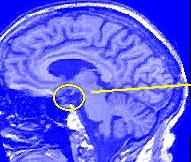

A. Brain: Interconnected neural circuits in the hypothalamus

- Lateral Hypothalamus (LH): Initiate eating

- Ventromedial Hypothalamus (VMH): Stop eating

- Arcuate Nucleus: Dual set of neurons: start & stop

- Paraventricular Hypothalamus (PVH): modulation of hunger